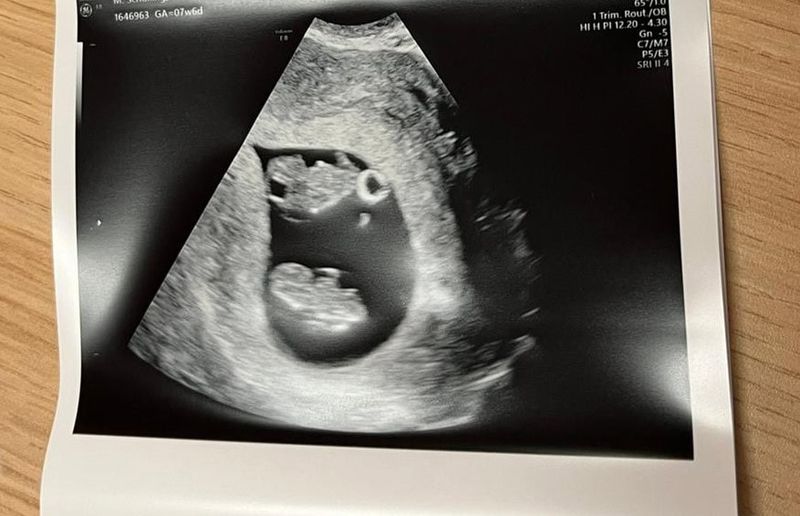

Meike: “We hadden niet eens tijd om het beeld van een tweeling te verwerken, toen we het slechte nieuws kregen. Ik had geen hoop meer op een goede afloop. De echoscopist zei: “jullie hebben nog een lange weg te gaan”

Ik zal niet de spanning opbouwen tot de volgende blog en de cliffhanger nu vast verklappen. Vier dagen later hadden we een uitgebreide echo in het ziekenhuis waar gelukkig geconstateerd werd dat ze wel allebei een eigen vruchtzak hebben, maar wel de placenta moeten delen (MCDA). Ik kan je wel vertellen dat door deze enorme rollercoaster en angst in deze paar dagen, er niet eens ruimte is geweest om het nieuws en de schok van überhaupt 2 baby’s ruimte te geven.